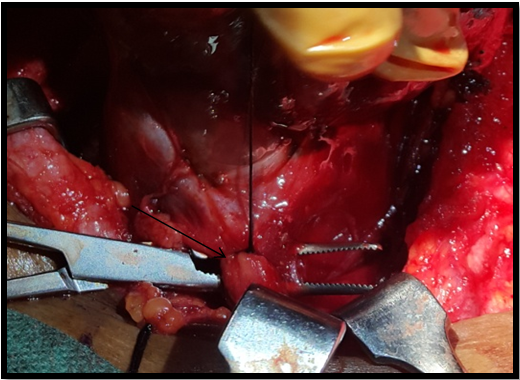

Figure 5A Multiple nodules on the surface of thyroid gland (arrow). Both the lobes dissected out after preserving parathyroid’s and RLN.

Figure 5B Retrosternal extension of the goitre visualized (arrow).

Figure 5C Retrosternal extension of the goitre with the lower pole at the level of thoracic inlet (arrow); being removed after gentle manipulation.

Figure 5D Ligating the thick thyroid ima artery. Note the engorged and thickened artery (arrow).

All patients underwent total thyroidectomy. Hereafter, the surgical technique employed and introp findings for the case with maximum retrosternal goiter (upto 10cm) are described. A low lying horizontal neck crease incision about 1-1.5cm above sternal notch was taken in a fully extended neck and the strap muscles retracted after the midline split. The dissection started from the superior pole from the left side being comparatively smaller to right side which was occupying the major part of retrosternal and making the inferior most part. This was done to ensure safety of atleast one RLN. Superior thyroid artery was identified and its branches ligated individually after identifying and preserving EBSLN. In view of large dimensions of the thyroid gland it was judged prudent to identify RLN via superior dissection after identifying the Cricothyroid (CT) joint. The superior parathyroids identified approximately 1cm caudally to CT joint and dorsal to RLN on both the sides and preserved. The inferior thyroid artery branches were ligated on the left side after preserving left parathyroid ventral to RLN but on the right side inferior thyroid artery was ligated in its main trunk. On Right, inferior parathyroid gland could not be identified. The left lobe along with its retrosternal extension was removed first. The right lobe which had the main retrosternal extension was dissected completely from the lateral side and then was cut into two halves after identifying the right RLN and the carotid sheath as to give more space for the manipulation of main retrosternal part. Blunt but gentle manipulation of the retrosternal extension in the superior mediastinum was done with the fingers above the plane of the trachea and the carotid artery. The assistant surgeon applied the traction superiorly and releasing it intermittently to avoid a shearing effect or excessive pressure on the great vessels. The manipulations were avoided lateral and below the carotid vessels or the trachea, to avoid devascularisation of trachea. The tracheo-esophageal groove was not violated. In the intrathoracic part all the thick bands or adhesions were palpated for any pulsation with the two fingers and they were dissected into thinner bands before their removal as to avoid any inadvertent trauma to any vessels. The lower pole was palpable intraoperatively and it was gently manipulated by the index finger to free any adhesions and the lobe was pulled up. A thickened thyroid ima artery was visualised and at the lower pole of the retrosternal extension was ligated and the entire retrosternal part delivered. Haemostasis was achieved and a surgical drain was placed and wound closed in layers. The entire thyroid gland was sent for HPE.